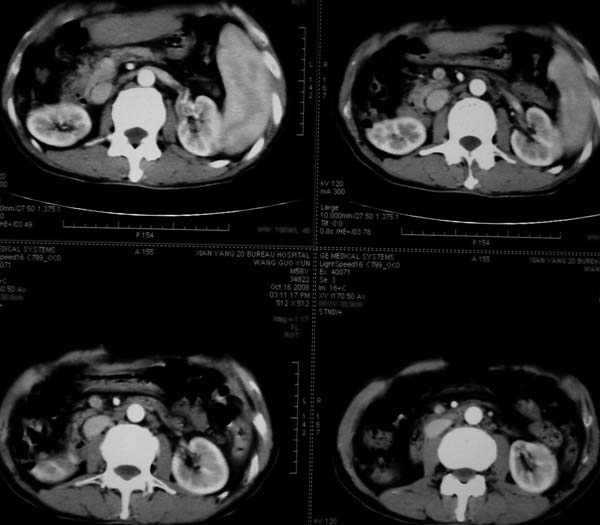

标题: CT16292:男,53岁,上腹部不适2月,B超发现肝内占位病变。 [打印本页]

标题: CT16292:男,53岁,上腹部不适2月,B超发现肝内占位病变。

符合肝ca增强,\"快进快出\";肝叶比例失常,右叶萎缩,肝裂增宽,脾大,肝硬化可能.

肝叶比例失调,左叶增大,肝裂增宽,脾脏增大,门脉增宽,肝右叶包膜下多发结节样阴影,增强虽说强化幅度不大,但还是符合快进快出特点;考虑肝硬化、脾大、结节型肝癌。胆管细胞癌多有延时强化、肝包膜凹陷征、周围胆管扩张等特点,本例明显不符;故不考虑。

动脉期静脉有显影 是否静脉有受侵改变啊